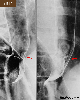

Several cases of typical esophageal papilloma.

X-ray

Benign epithelial tumor/papilloma